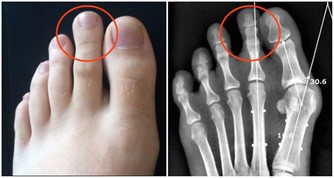

為了給他最正確的建議,我先幫他量了血壓,結果為168/98 mmHg。

(圖片來源:資料圖庫)